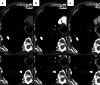

Image-guided percutaneous lung ablation has proven to be a valid treatment alternative in patients with early-stage non-small cell lung carcinoma or oligometastatic lung disease. Available ablative modalities include radiofrequency ablation, microwave ablation, and cryoablation. Currently, there are no sufficiently representative studies to determine significant differences between the results of these techniques. However, a common feature among them is their excellent tolerance with very few complications. For optimal treatment, radiologists must carefully select the patients to be treated, perform a refined ablative technique, and have a detailed knowledge of the radiological features following lung ablation. Although no randomized studies comparing image-guided percutaneous lung ablation with surgery or stereotactic radiation therapy are available, the current literature demonstrates equivalent survival rates. This review will discuss image-guided percutaneous lung ablation features, including available modalities, approved indications, possible complications, published results, and future applications.